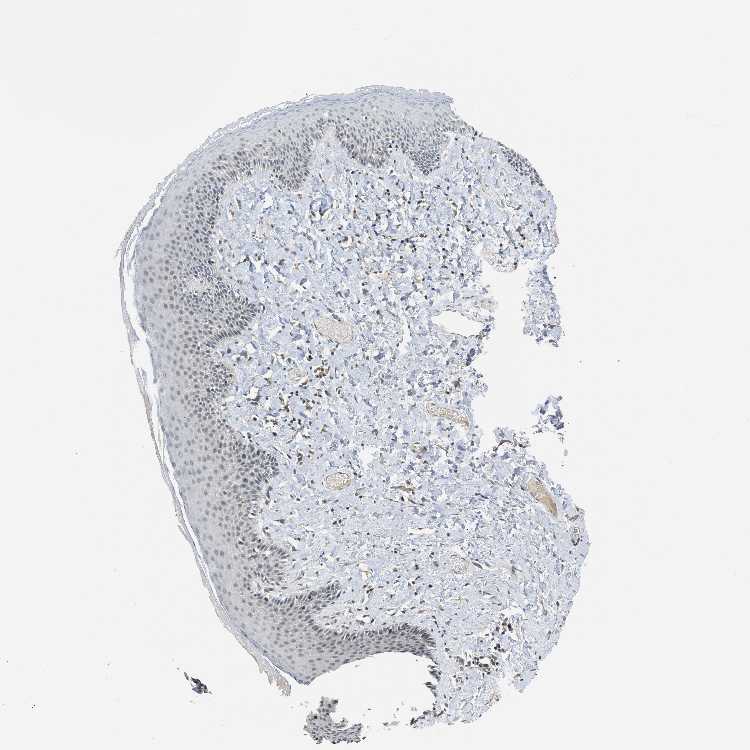

SKIN 1 - Antibody stainingi

Antibody staining in the annotated cell types in the current human tissue is reported as not detected, low, medium, or high, based on conventional immunohistochemistry profiling in selected tissues. This score is based on the combination of the staining intensity and fraction of stained cells.

Each image is clickable and will lead to virtual microscopy that enables deeper exploration of all samples and also displays staining intensity scores, fraction scores and subcellular localization as well as patient and tissue information for each sample.

Antibody HPA001757

Langerhans Not detected

Fibroblasts Not detected

Keratinocytes Low

Melanocytes Not detected